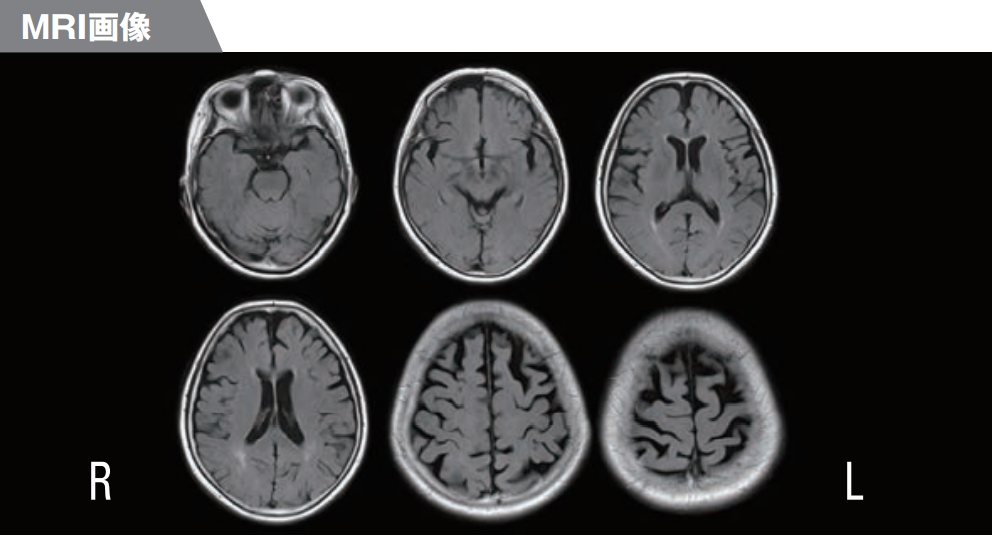

脳萎縮は、次のような脳画像スキャンで明らかになります。

- コンピューター断層撮影 (CT) は、さまざまな角度からの X 線画像を使用して脳の詳細な画像を作成します。

- 磁気共鳴画像法 (MRI) は、脳を短時間磁場にさらした後、フィルム上に脳画像を作成します。